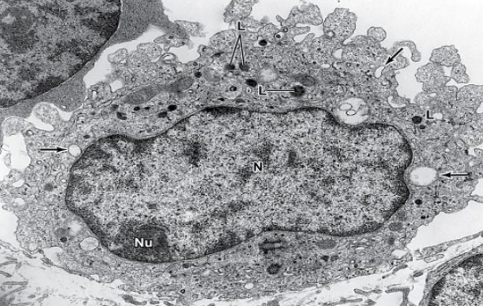

What are the cells of CT characterized by?

oval nuclei with prominent nucleoli and fine chromatin

many thin cytoplasmic processes

abundance and viscous extracellular matrix

What does a fibroblast look like?

abundant and irregular branched cytoplasmic processes

ovoid large nucleus with large nucleolus

abundant RER and well-developed golgi

fibroblast

fibrocytes and fibroblasts